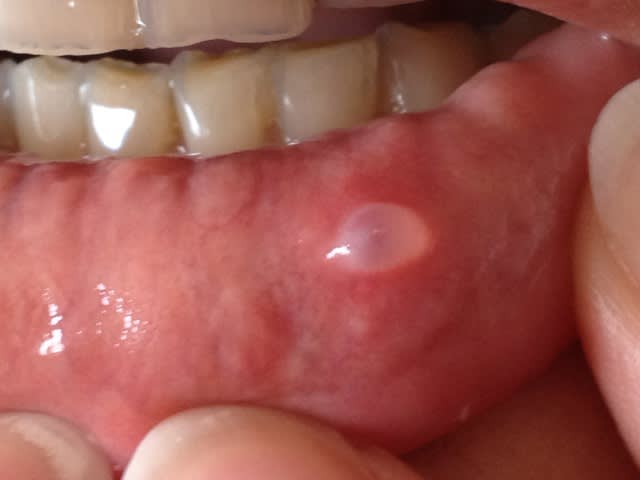

voici une jolie photo,la patiente est une jeune femme de 35 ans, non fumeuse avec une très bonne hygiène,

elle présente régulièrement des lésions sur la lèvre inférieure

calcul glande salivaire accessoire

probalement un kyste muccoîde

+1 ....= Mucocèle

mucocèle dont l'exérèse est plus simple qu'une dds mais beaucoup mieux rémunérée.

en principe c'est DC 15 : "éxérèse d'une tumeur bénigne de la bouche" selon NGAP